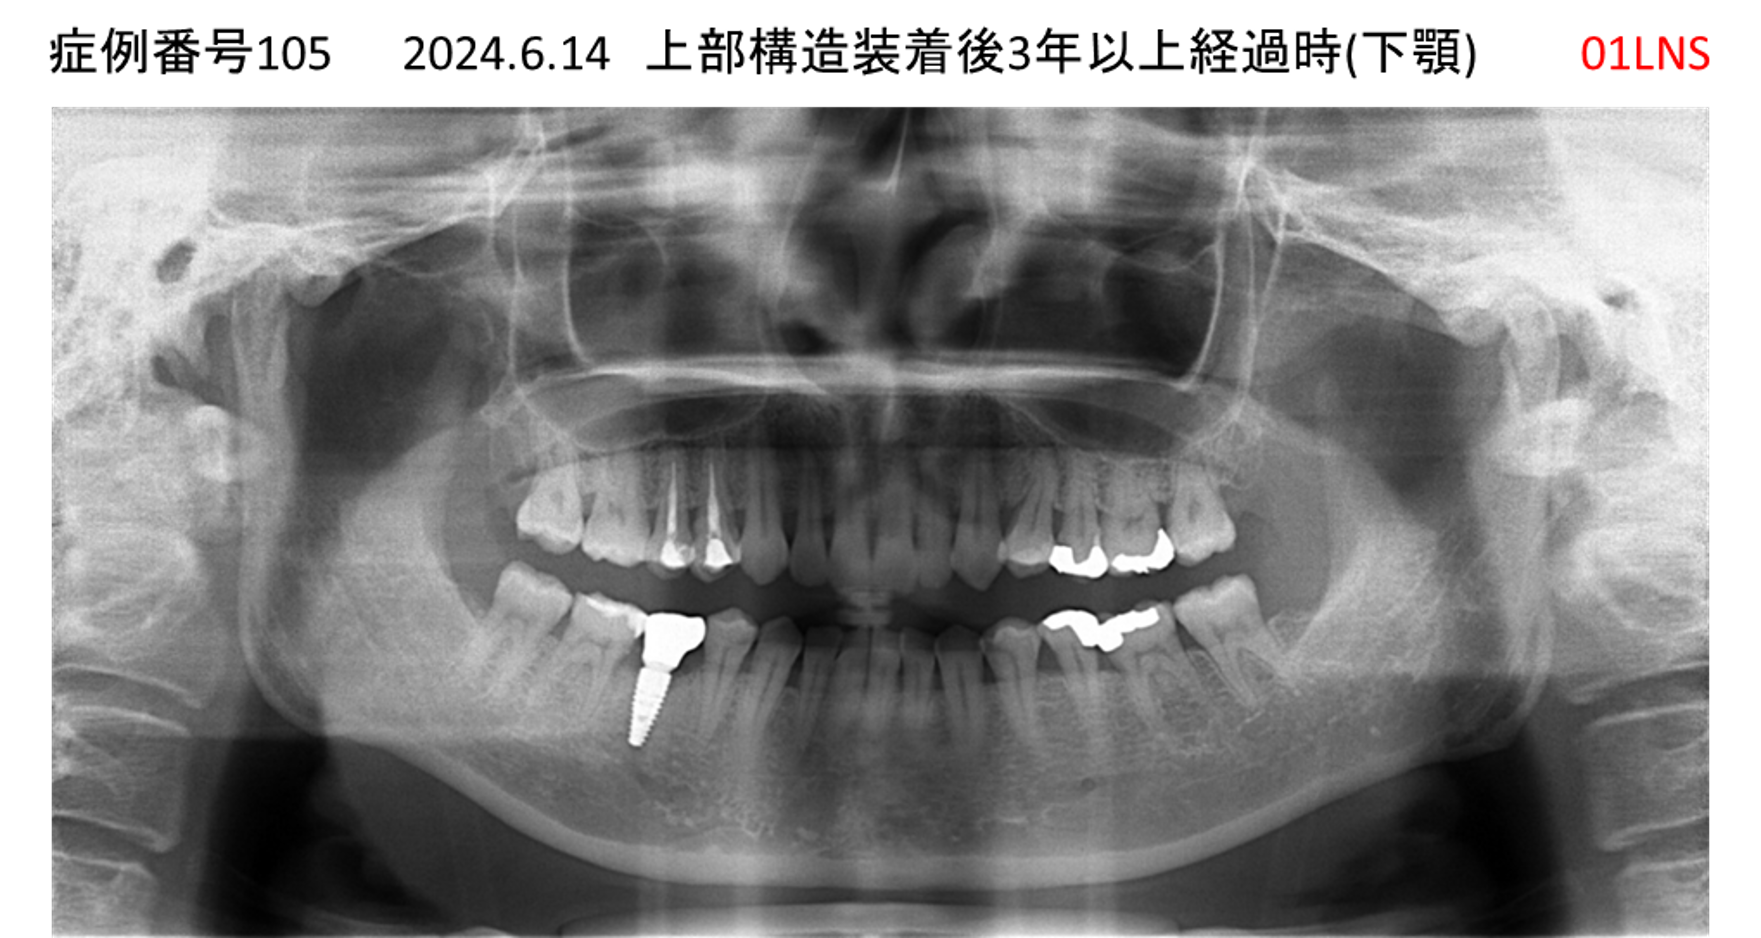

奥歯で噛めない患者様のインプラント症例

| 治療名称 |

インプラント |

| 治療費用 |

150万円+税 |

| 治療期間 |

3か月 |

| 患者さんの症状(主訴) |

奥歯で噛めない。食事がとれない。 |

| 治療内容 |

| 治療結果 |

食事に困らない。何でも食べられる。 |

| 治療の注意点(リスク/副作用) |

インプラントが壊れたら再治療が必要 |